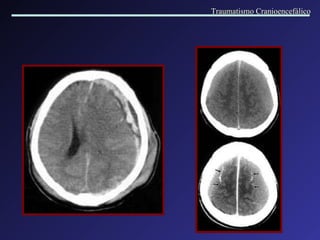

Hemorragia Extra axial Hematoma Subdural Agudo   Formados entre a duramater e a aracnóide, por lesão de veias córtico-meníngeas. Este espaço é facilmente dilatável, possibilitando grandes acúmulos de sangue. Causas: quedas ou agressão. Lesões associadas. Intervalo lúcido. Coleção em crescente, com efeito de massa variável. A cirurgia normalmente está indicada. Traumatismo Cranioencefálico

Hematoma Subdural   Agudo Traumatismo Cranioencefálico

Traumatismo Cranioencefálico

Hematoma Subdural Agudo em regiões fronto-temporo-parietal D, com importante desvio da linha mediana (tumefação hemisférica) e hematoma epidural associado na região parietal E. Traumatismo Cranioencefálico